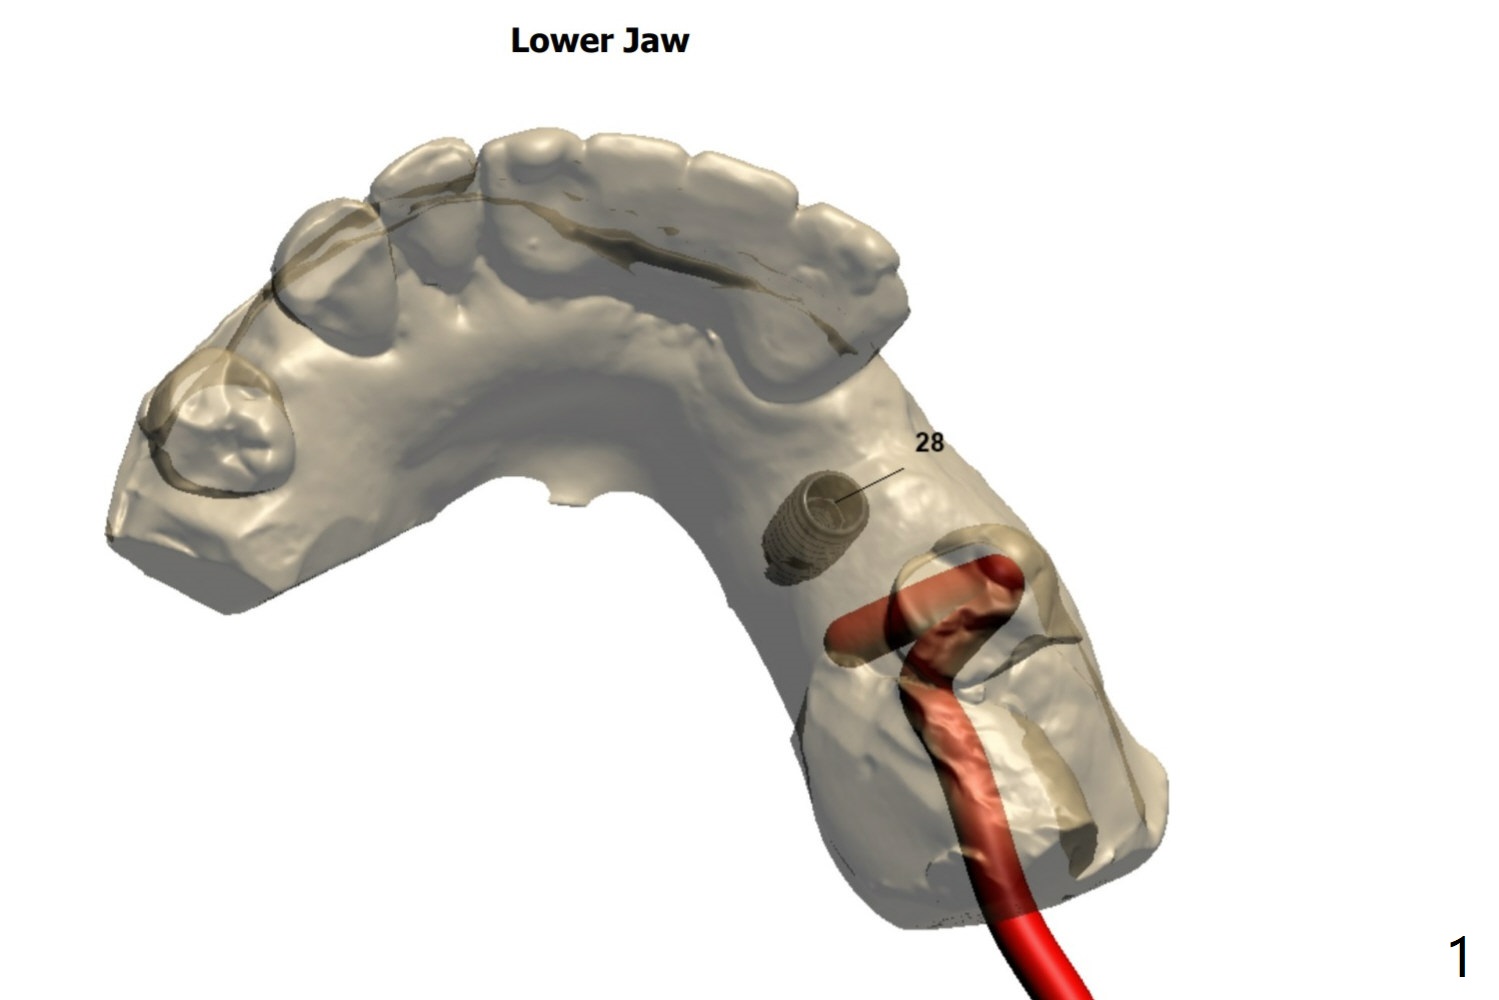

植骨低骨密度

53岁男,左下4(28号牙)需要植牙,拔牙而没有植骨后一年,由于牙槽窝骨质密度不均匀,可能低。稍微使用环形钻头后,形成标记,切开探查,使用自体骨做必要植骨:植牙区和第二前磨牙近中。植入FC植体4.5x11毫米,可以稍微浅:.5-1.0毫米,同时减少牙龈厚度,颊侧放置骨粉